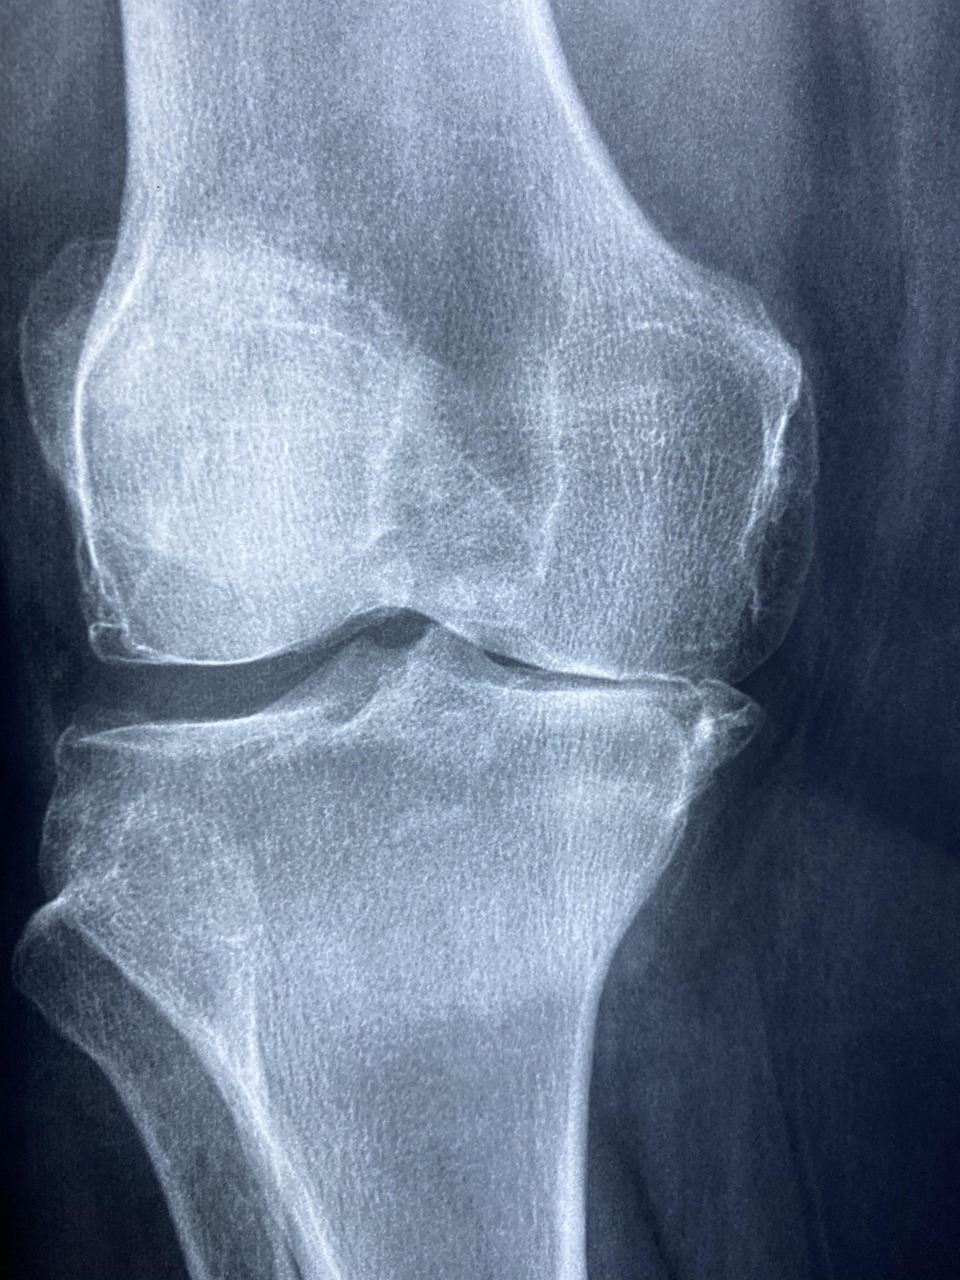

글루코사민은 본래 갑각류의 키틴에서 추출되는 아미노당으로, 관절 연골의 구성 성분 중 하나입니다. 다양한 동물실험과 세포 연구를 통해 글루코사민이 연골세포의 생성과 회복을 돕는다는 결과가 확인되었습니다. 특히, 연골 내 프로테오글리칸과 콜라겐 생성을 자극하여 관절의 유연성과 탄성을 유지하는 데 도움이 된다는 것이 주요 결과입니다. 국제적으로 권위 있는 저널인 The Lancet 및 Osteoarthritis and Cartilage 등에서는 글루코사민에 대한 체계적 문헌 고찰(Systematic Review)을 통해 일정 수준의 효과를 인정하고 있습니다. 특히 관절염 초기 환자에게 있어 통증 감소 효과가 있는 것으로 보고되었으며, 장기 복용 시 관절 공간 협착의 진행을 지연시킨다는 데이터도 있습니다. 하지만 과학계에서는 여전히 글루코사민의 효과에 대한 의견이 분분합니다. 일부 연구는 위약(Placebo)과 비교했을 때 유의미한 차이를 발견하지 못했다고 보고하고 있으며, 이는 복용자의 상태, 복용 기간, 용량 등 여러 요인에 따라 결과가 달라질 수 있음을 시사합니다.

글루코사민은 전 세계적으로 다양한 임상 시험을 통해 검증되어 왔습니다. 대표적인 임상 중 하나인 GAIT 연구(Glucosamine/Chondroitin Arthritis Intervention Trial)는 미국 국립보건원(NIH) 주도로 진행된 대규모 무작위 이중맹검 연구로, 약 1,500명의 무릎 관절염 환자를 대상으로 글루코사민, 콘드로이친, 복합 복용의 효과를 비교했습니다. 결과적으로, 전체 참가자 중에서는 위약 대비 통계적으로 유의미한 차이가 없었지만, 중등도 이상의 통증을 가진 하위 그룹에서는 글루코사민과 콘드로이친을 병용했을 때 상당한 통증 감소 효과가 관찰되었습니다. 이는 단순한 통계 수치 이상의 임상적 의미를 갖는 결과로 해석되고 있습니다. 또한 유럽과 아시아에서도 다수의 임상 실험이 수행되었으며, 특히 유럽 관절학회에서는 글루코사민 황산염(Glucosamine Sulfate)의 경우 관절 통증 완화 및 기능 향상에 긍정적인 평가를 내리고 있습니다. 단, 글루코사민 HCl(염산염) 형태의 경우 효과가 떨어지는 경향이 있다는 연구도 존재하여, 제품 선택 시 성분 형태를 주의 깊게 살펴볼 필요가 있습니다. 이러한 결과들을 종합하면, 글루코사민은 일정 조건하에서 충분히 관절 건강 개선에 도움을 줄 수 있는 보충제이며, 복합 성분 및 복용 시기, 용량 등이 효과를 좌우하는 중요한 변수로 작용합니다.